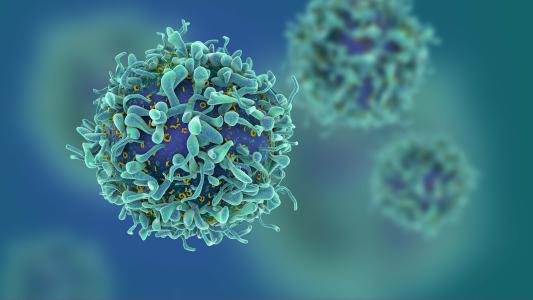

"T cells" could provide immunity after antibodies fade

T cells that combat SARS-CoV-2 have been discovered in people who never had COVID-19, potentially putting natural herd immunity within our grasp.